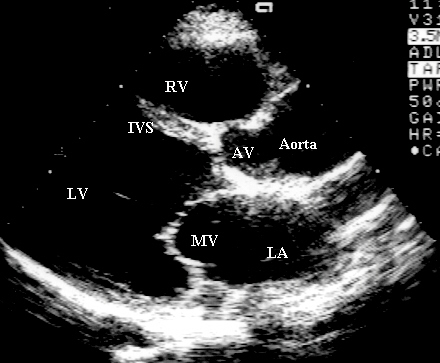

Echocardiographic image of the heart

The four heart valves are:

- the tricuspid valve, located

between the right atrium and right ventricle (RV);

- the pulmonary or

pulmonic valve, between the

right ventricle and the pulmonary artery;

- the mitral valve (MV), between the left

atrium (LA) and left ventricle; and

- the aortic valve (AV), between the

left ventricle (LV) and the aorta. Each valve has a set of flaps (also

called leaflets or cusps).

The mitral valve has two flaps; the others have

three. Under normal conditions, the valves permit blood to flow in